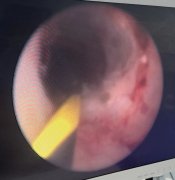

【精准“导航”+无痛定位】南通六院胸外科黑科技让“刁钻”肺结节无处可藏!

肺结节位置太深、藏在骨头缝里? 传统定位又疼又有辐射? 别担心!南通六院胸外科黑科技 CT三维数据融合式经皮穿刺导航定位术 2分钟精准锁定病灶,...